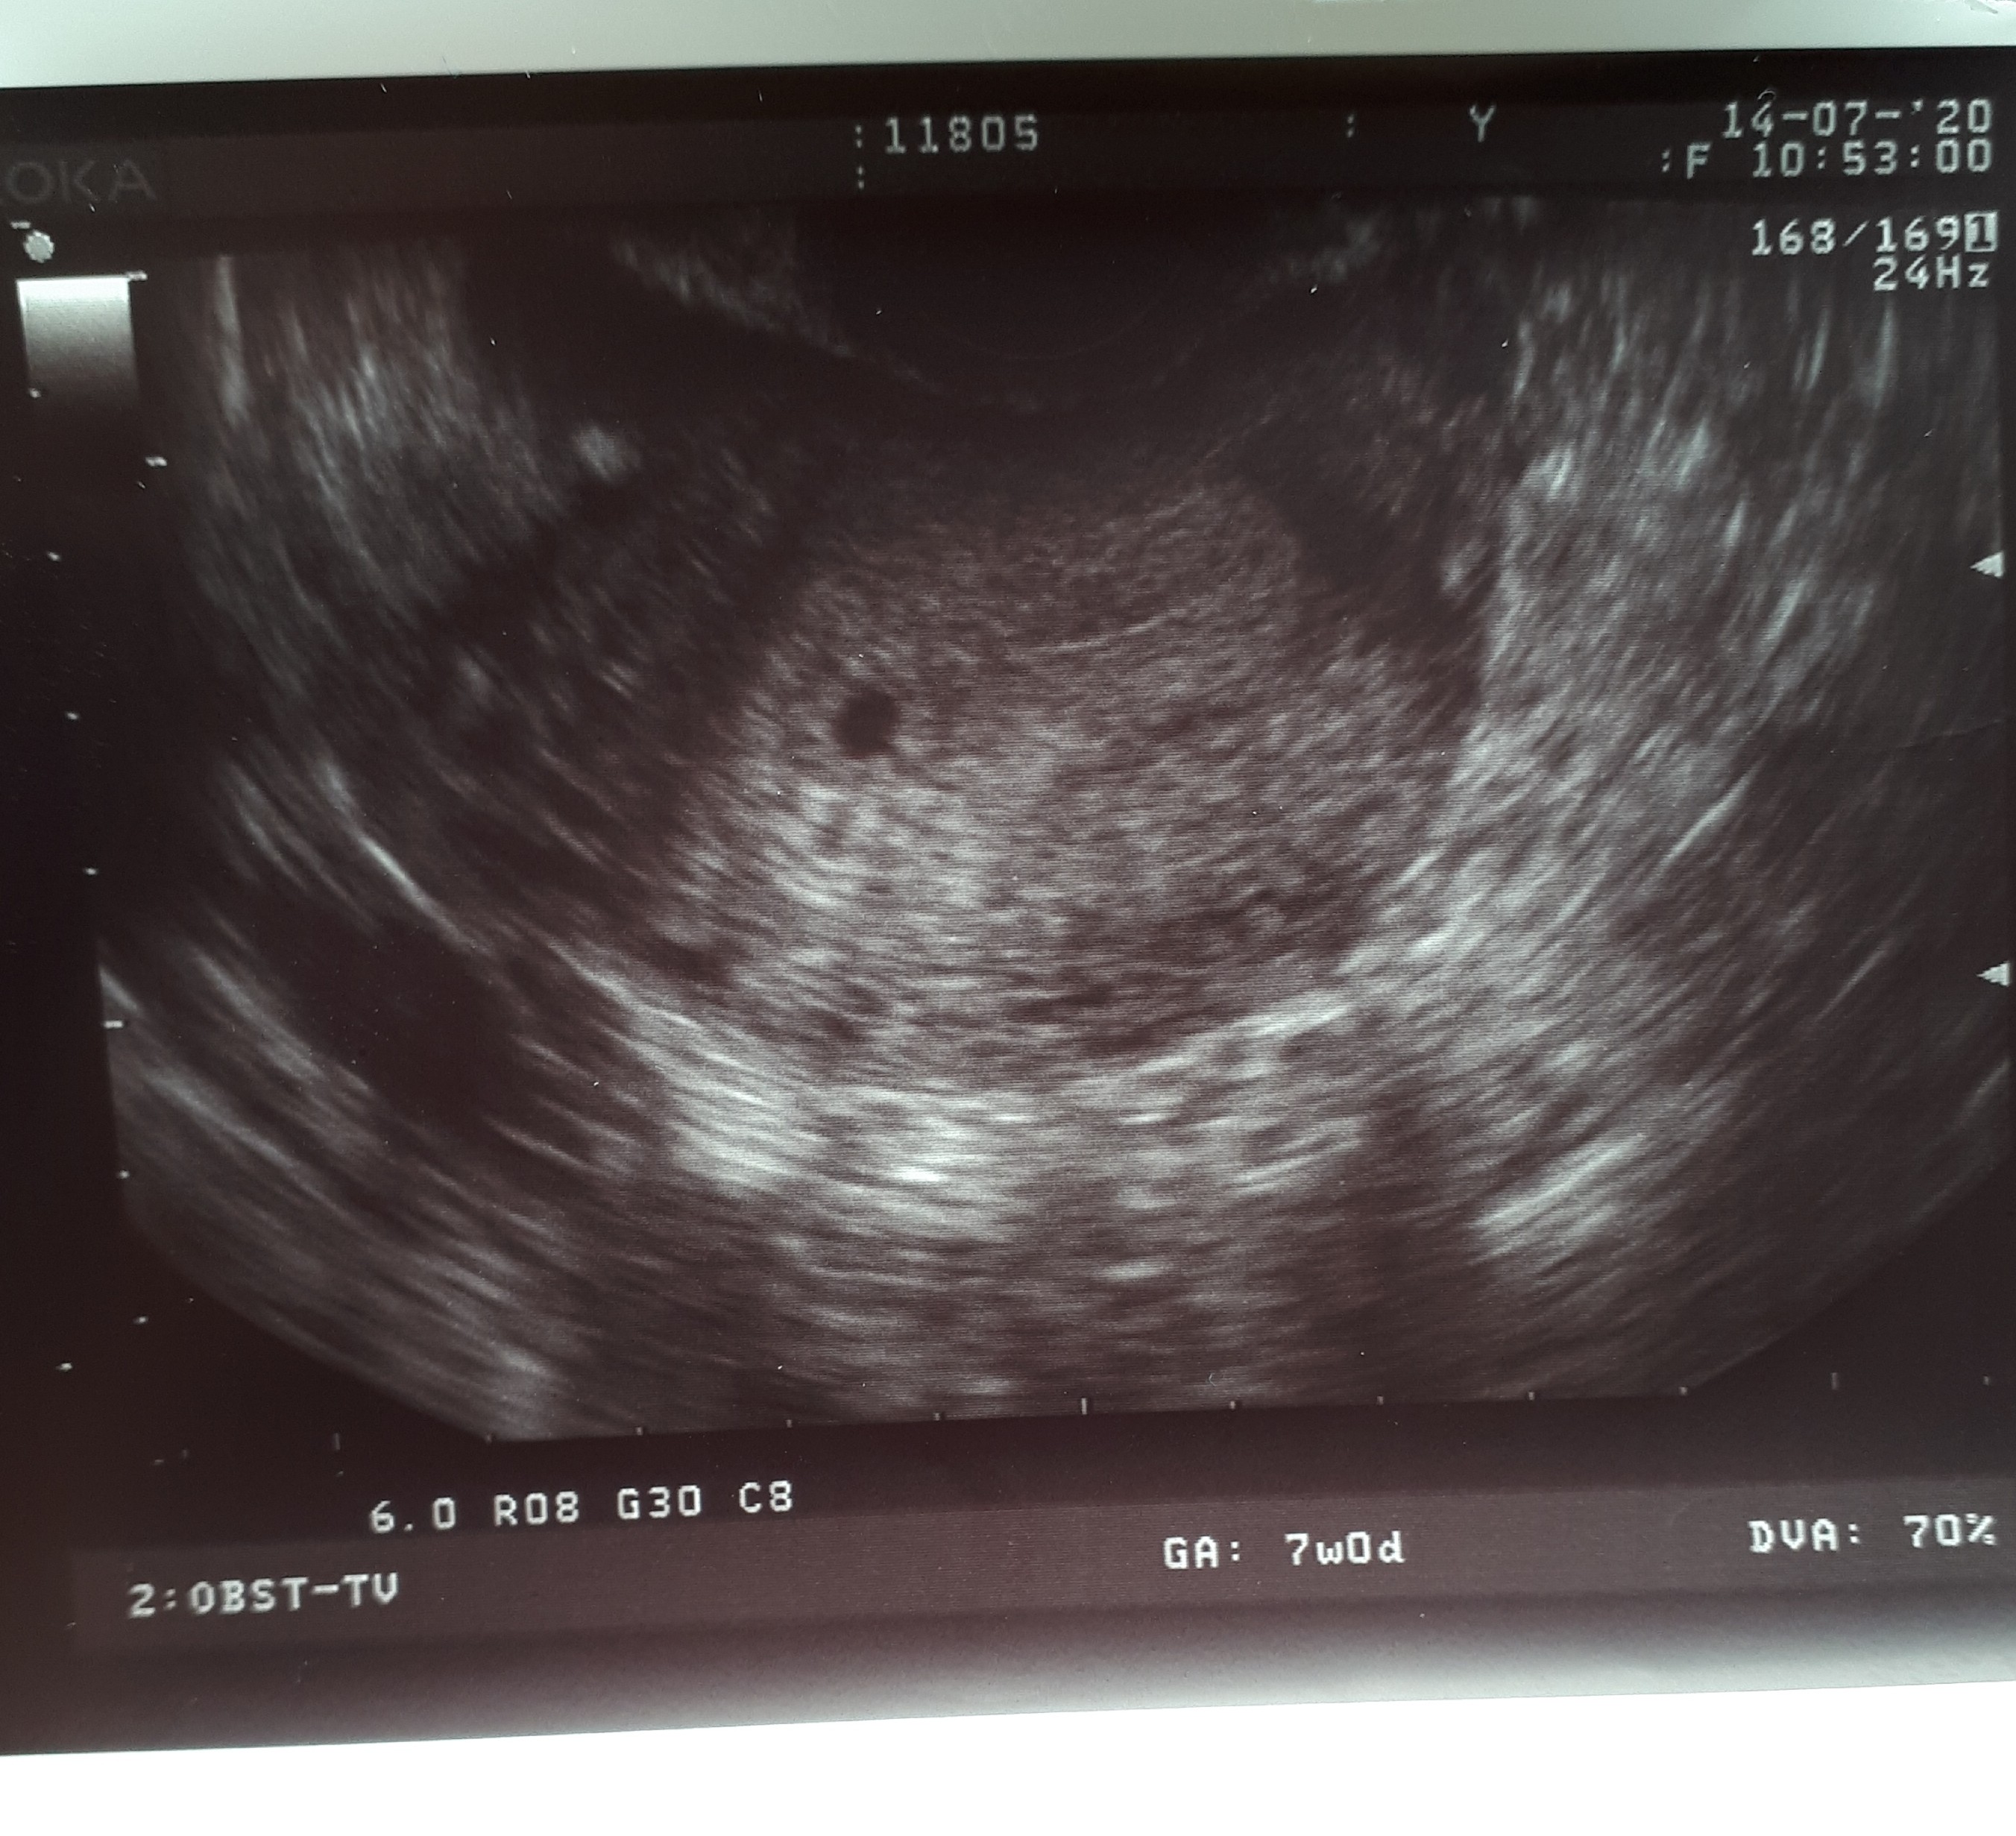

Mnie też czekają badania prenatalne, tzw. test potrójny czyli test PAPP-a, Wolna podjednostka beta HCG i Przezierność karkowa. U mnie uwarunkowaniem jest wiek, mam 36 lat. Ale będąc w 1 ciąży 11 lat temu również skierowano mnie na badania prenatalne. Wynik wskazał na duże ryzyko zespołu Downa i zrobiono mi amniopunkcję. Na szczęście syn okazał się zdrowy i spokojnie cieszyliśmy się pozostałym czasem do rozwiązania. Wiem, że wyniki tych testów to w dużym stopniu statystyka, ale wychodzę z założenia , że należy korzystać z dostępnych możliwości diagnostycznych, nigdy nie wiadomo kiedy uratują życie naszego maluszka.Czy jest tu ktoś w podobnej sytuacji?